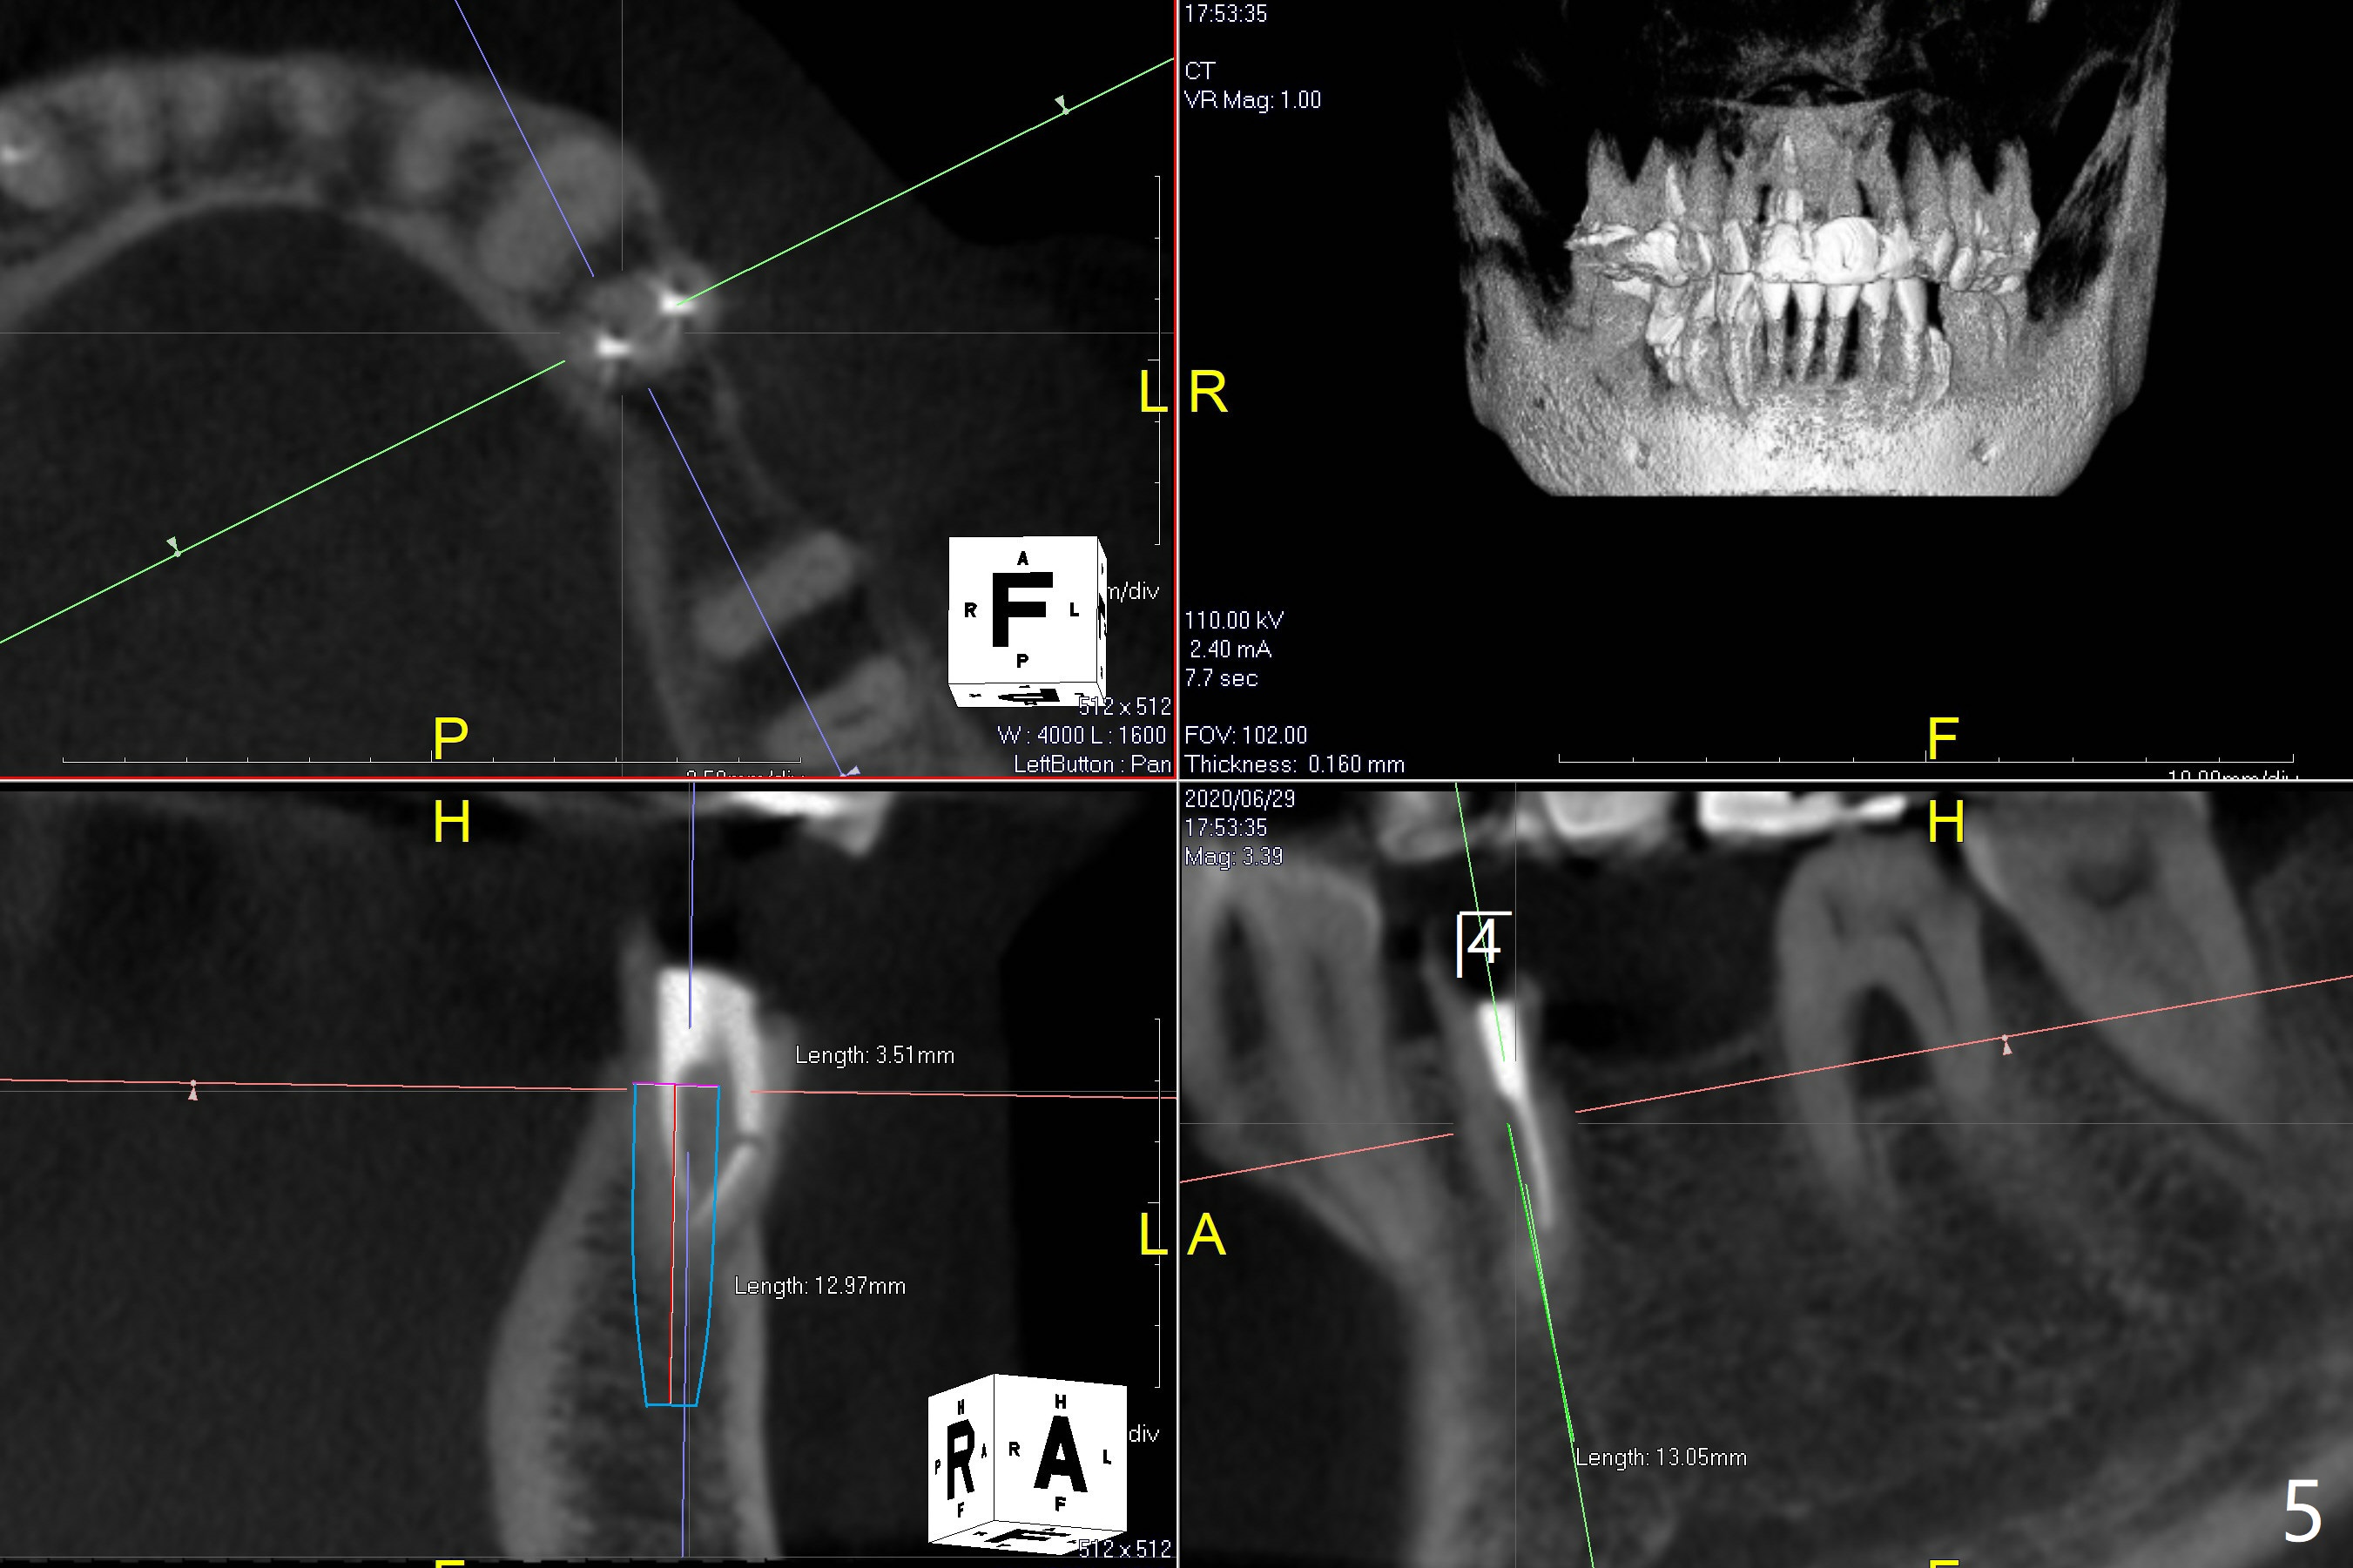

63岁女对肾上腺素和90%以上抗生素过敏,左上5(短根,巨大根尖阴影,图一),左下6(根分叉感染,远中龋齿(图二:*),左下4(牙齿断裂略微龈下:图二,五)似乎很难保留,左下5骨质宽度,高度也允许植牙(图四)。由于左上5需要提升术,可能出现上颌窦感染,Z Pack是否引起过敏反应不确定,拔牙植骨与提升植牙分期做(术前拍摄根尖片)。而下颌一期完成。